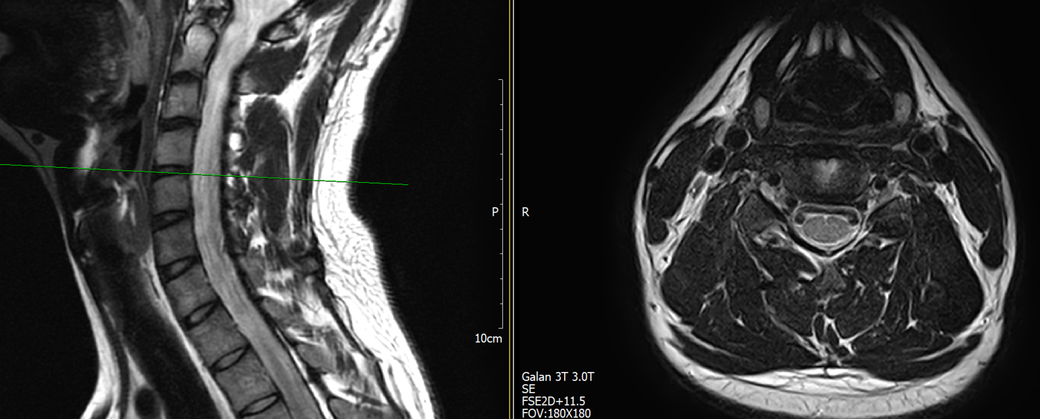

목과 오른쪽 어께 통증이 있어 mri를 찍어왔는데, 사진에서 의심되는 부분 있을까요?

통증은 10년 정도 되었고, 통증 의학과 가서 신경차단술 2회 받은 상태입니다.

토요일에 mri 찍고 주말이라 물어볼 곳이 없어 먼저 여기에 사진 올려봅니다. 답변 부탁드립니다.

• 1번 째 사진

MRI만 보면 굉장히 깨끗한 목입니다.

디스크탈출은 없고 신경뿌리가 압박될만한 모습도 전혀 보이지 않습니다.

지금은 MRI에서 잘 보이지 않는 디스크내장증일 가능성이 높아보이며 경추전만 자세를 잘 유지해주시는게 가장 큰 도움이 되겟습니다.